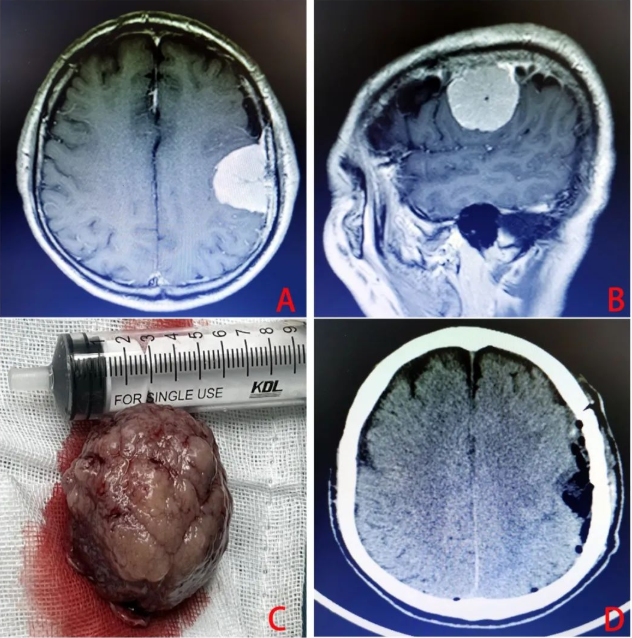

该肿瘤约鸡蛋大小,刚好生长在左侧大脑中央区(优势半球的运动及感觉中枢)上,肿瘤占位效应明显,脑组织受压移位。

在马俊的带领下,历经3小时,手术取得圆满成功。

术后患者病情平稳,未出现肢体运动及感觉障碍,恢复良好,在病区继续治疗。

脑膜瘤是神经外科常见的肿瘤之一,约占颅内肿瘤的15.31%,仅次于胶质瘤。中老年人较多,女性稍多于男性。脑膜瘤原发于蛛网膜内皮细胞,凡属颅内富于蛛网膜颗粒与蛛网膜绒毛之处皆是脑膜瘤的好发部位,矢状窦旁,大脑凸面,大脑镰旁者多见,其次为蝶骨嵴、鞍结节、溴沟、小脑桥脑角与小脑幕等部位,大部分患者是在体检过程中发现。

脑膜瘤的临床特点是发病缓、病程长,不同部位脑膜瘤可有不同的临床表现,因成年人发病较多,故凡成年人有慢性头痛、精神改变、癫痫、一侧或两侧视力减退甚至失明、共济失调或有局限性颅骨包块等,特别是伴有进行性加重的颅内压增高症状时,要考虑脑膜瘤的可能性。诊断脑膜瘤,其有重要参考价值的检查包括颅骨平片、CT扫描、头颅MRI检查。不仅可以达到定位,还可以了解肿瘤大小和定性。

对脑膜瘤的治疗,以手术切除为主。原则上应争取完全切除,并切除受肿瘤侵犯的脑膜与骨质,以期根治。脑膜瘤属脑实质外生长的肿瘤,大多属良性,如能早期诊断,在肿瘤尚未侵犯周围的脑组织与重要颅神经、血管受到损害之前手术,应能达到全切除的目的。但是有一部分晚期肿瘤,尤其是深部脑膜瘤,肿瘤巨大,与神经、血管、脑干及丘脑下部粘连大紧,这些神经血管不易分离,这种情况下,不可勉强全切,以免加重脑和颅神经损伤以及引起术中大出血的危险,甚至招致病入死亡或严重残疾。对无法手术切除的晚期肿瘤,行瘤组织活检后,仅作减压性手术,以延长生命,恶性者可辅以放疗。(图文/神经外科 马元施)